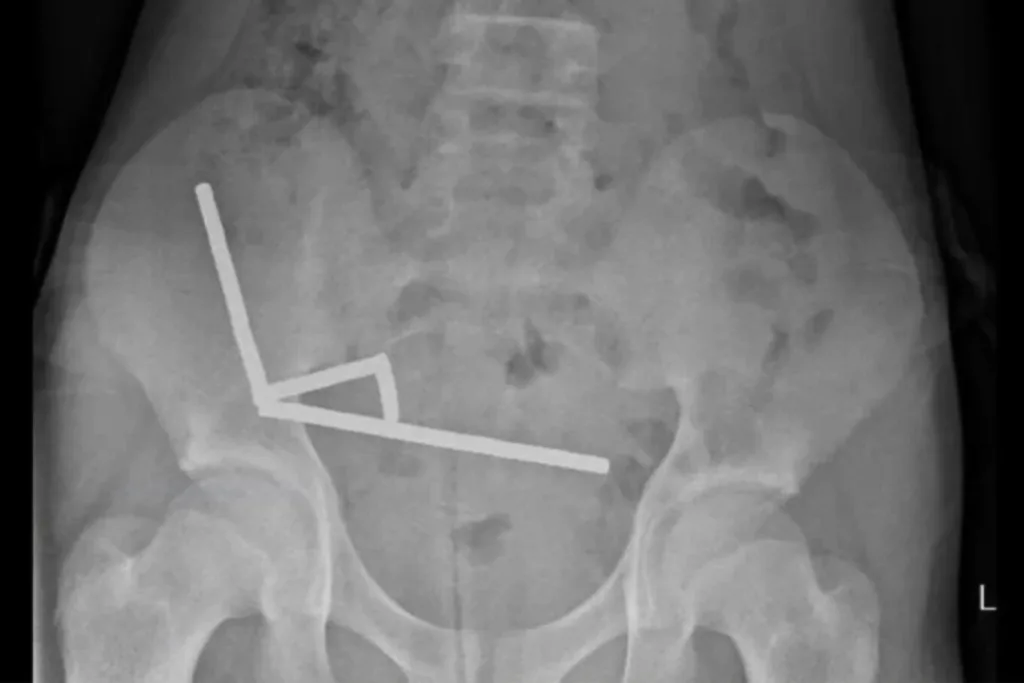

Η ακτινογραφία έδειξε ότι οι μαγνήτες είχαν συσσωρευτεί σε τέσσερις ευθείες γραμμές μέσα στα έντερα του παιδιού. Βρίσκονταν σε ξεχωριστά μέρη του εντέρου και είχαν κολλήσει μεταξύ τους λόγω μαγνητικών δυνάμεων.

Οι γιατροί ανέφεραν ότι η πίεση των μαγνητών είχε προκαλέσει νέκρωση σε τέσσερα σημεία του λεπτού εντέρου και του τυφλού εντέρου του αγοριού, το οποίο αποτελεί μέρος του παχέος εντέρου. Οι χειρουργοί επενέβησαν για να αφαιρέσουν τον νεκρό ιστό και να ανακτήσουν τους μαγνήτες.